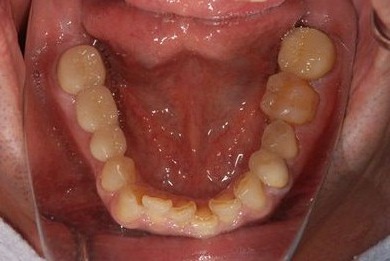

インプラント治療+セラミック治療+歯肉歯槽骨整形術

| 性別/年齢 | 男性 / 47歳 | ||||||||||||||||||||||||||||||||

| 主訴 | 悪いところの治療と、歯をきれいにしたい。 | ||||||||||||||||||||||||||||||||

| 治療方針 | 右下奥、保存不能な歯を抜歯し、インプラント治療にて、機能的・審美的回復を行う。 | ||||||||||||||||||||||||||||||||

| 治療内容 | インプラント2本、メタルボンドセラミッククラウン9本(メタルボンド用土台6本)、ハイブリッドセラミッククラウン2本(セラミック用土台2本)、ハイブリッドセラミックインレー5本、歯肉歯槽骨整形術 | ||||||||||||||||||||||||||||||||

| 治療期間 | 2年9ヶ月 |